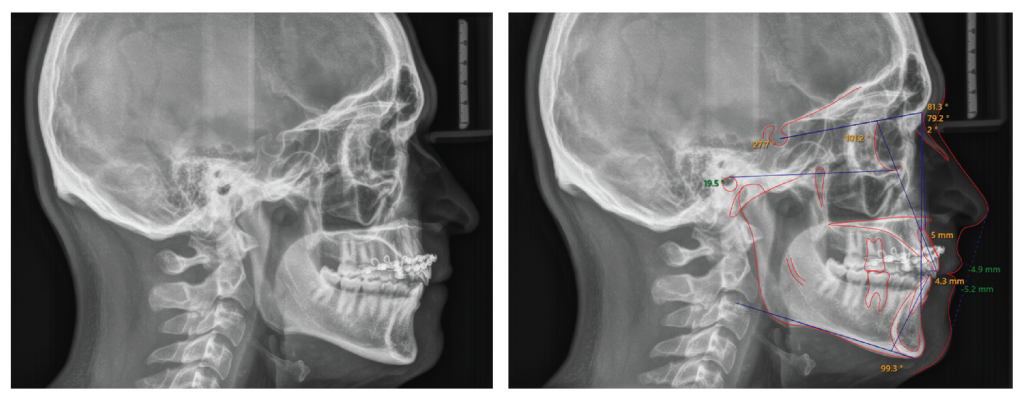

Lateral cephalometric analysis (Figure 8 and Table I) indicates that we maintained the sagittal (ANB = 1.6°) and vertical relation (FMA = 19.9°) of the jaws, and retroclined and extruded upper incisors.

Figure 8: Post-treatment lateral cephalometric radiograph. Post-treatment cephalometric radiograph shows an ideal overjet and overbite, slight retroclination of the maxillary incisors (98.5°) and minimal proclination of the mandibular incisors (100.2°). The sagittal and vertical relation of the jaws were maintained.